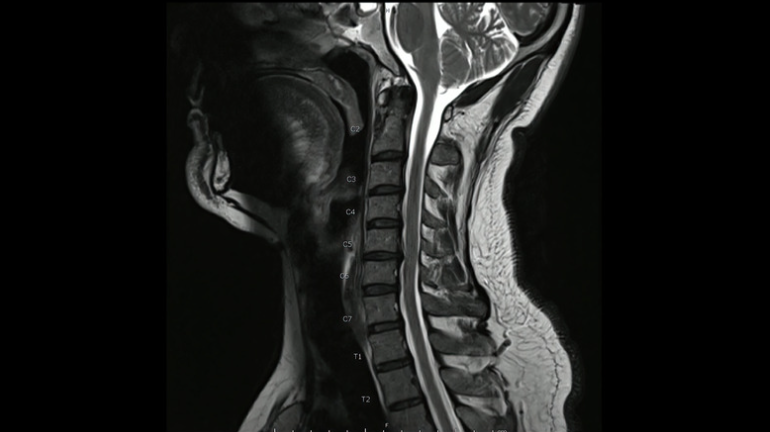

首のMRIで神経の圧迫所見がある場合確定診断します。

頚椎症の診断はヘルニア同様、痛みしびれの範囲、レントゲン、MRIで行います。レントゲンで骨と骨の隙間が狭くなっていたり、骨がずれているなどの変性所見(加齢性の変化)があると頚椎症を考えます。

また頸椎MRIで脊髄の圧迫と信号変化があると頚髄症を強く考えます。